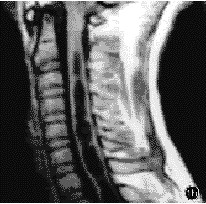

本组特发性脊柱侧凸患者占总病例数的74.7%(464/621),与文献报道的75%~80%相一致。但如果单独分析9~28岁常见手术年龄组的脊柱侧凸病例,则发现非特发性脊柱侧凸的构成百分比明显上升,由总病例数的25.3%(157/621)上升至34.0%(133/391)。表明在9~28岁这一常见手术年龄组内,有1/3的脊柱侧凸患者为非特发性脊柱侧凸。目前,国内外尚未见关于这一年龄组脊柱侧凸病因构成百分比的报道。史亚民等[14]和吴之康等[15]分别报告了177例和218例进行手术矫治的脊柱侧凸病例,其中非特发性脊柱侧凸者分别占30%和34%,说明在需要接受手术矫治的脊柱侧凸患者中约有1/3为非特发性脊柱侧凸者。本组非特发性脊柱侧凸构成百分比较高,可能与以下因素有关:(1)详细的全身体检发现了隐匿的神经系统体征,提示为非特发性脊柱侧凸。本组有2例腹壁反射减弱,3例有未曾引起注意的浅感觉减退而无任何其他神经系统的症状与体征,原诊断为特发性脊柱侧凸,经MRI检查发现有Chiari畸形和脊髓空洞(图1)。(2)对脊柱侧凸X线片特征的认识提高。我们经过X线片及体检筛选后,对胸椎“特发性”左侧凸或胸椎后突性侧凸病例进行MRI检查,发现部分患者合并有脊髓空洞或脊髓发育性畸形(图2)。(3)对脊柱侧凸发病原因和自然转归的认识加深。如对成年后侧凸仍明显加重或伴关节松弛、肝、脾肿大的脊柱侧凸患者,经进一步检查,确诊为神经肌源性脊柱侧凸(图3)和粘多糖病源性脊柱侧凸。

图1患者男,16岁1aX线正位片显示为“典型”特发性脊柱侧凸

1bMRI检查发现Chiari畸形合并脊髓空洞